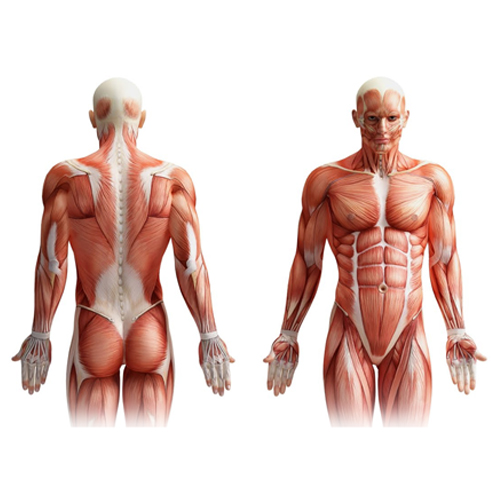

The muscles of respiration

Intercostal muscles are arranged in 2 layers between the ribs, external and internal intercostals muscles. When they contract they pull the ribs outwards and upwards therefore enlarging the thoracic cavity.

The diaphragm forms the floor of the thoracic cavity. When it contracts it moves downwards and enlarges the thoracic cavity.

The diaphragm and intercostals muscles contract at the same time to enlarge the thoracic cavity.